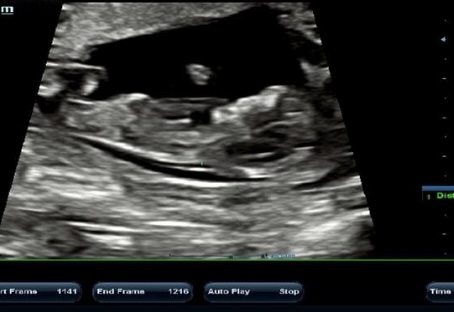

سلام بیاین حدس بزنین جنسیتش چیه؟

سونو ان تی هست۱۲هفته۴روزم